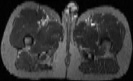

Visible Human male: Sectio transversalis 1954

CT

NMR

Pd                          / T2 \                         T1